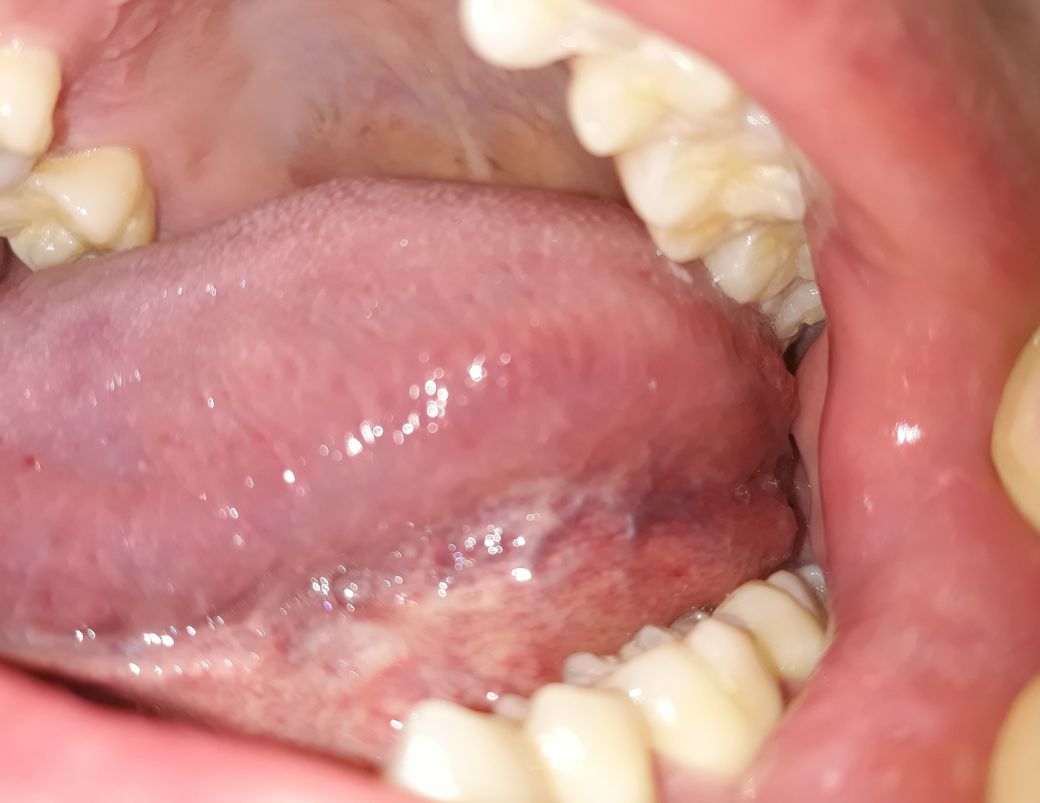

혓바닥 아래 상태가 정상인가요???

양치하다가 혓바닥 옆쪽 아래를 봤는데 잔핏줄도 많이 보이고 중간에 색깔도 군데군데 누런거같기도한데 만져보니깐 부드럽고 통증이나 불편한건 없습니다. 괜찮은건가요?

• 1번 째 사진

입 구석구석을 살펴보셨네요. 사진 올려주신 것만 봐서는 특별한 이상은 없어 보입니다. 증상도 없으니 괜찮다고 보셔도 되구요.